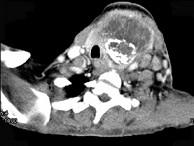

问题 女,64岁,双甲状腺占位40余天。如图所示甲状腺病灶应诊断为()

选项 A.结节性甲状腺肿 B.甲状腺腺瘤 C.甲状腺癌并淋巴结转移 D.甲状腺转移瘤 E.甲状腺结核

答案 C